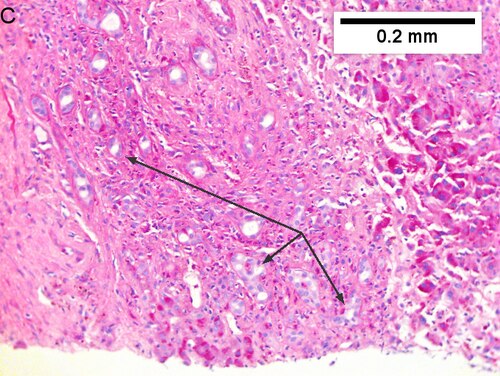

Cholangiocarcinoma, intrahepatic, with associated abscess. A. Aberrant spaces (arrows) contrast with the scar to the regions left and, at right, hemosiderin laden macrophages amid granulation tissue [40X]. B1. Disorderly spreading glands (black arrows) associated with atypical single cells (cyan arrows) have nuclei that contrast with those of the normal bile duct (blue arrow) with its associated artery (green arrow) [200X]. C. PAS without diastase shows disorderly spreading, aberrantly shaped glands at left (arrows) and red degenerated hepatocytes to right [200X]. D. PAS with diastase shows proliferating bile ducts to left, one with highly aberrant nuclei (black arrow), highly atypical cells at middle (green arrows) with sometimes incomplete (cyan arrows) acini, and normal liver at right (blue arrow) [200X]. E. CK7 immunostain shows proliferating glands at left and a disorderly spread of single cells and cell groups at right, amid hepatocytes [200X]. F. CK7 immunostain at higher power shows the stained cells have aberrant nuclei [400X].